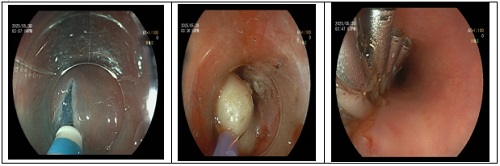

内镜下开展的手术

3.内镜下粘膜剥离术